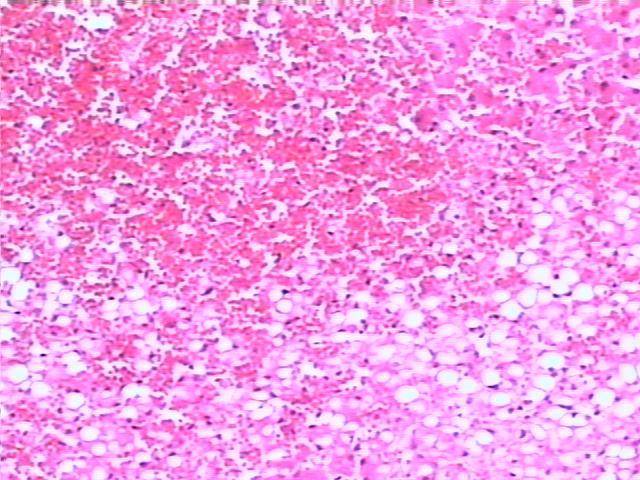

肺褐色硬化 brown induration of lung

1.肺泡壁增厚,肺泡壁毛细血管扩张充血

2.部分肺泡腔内含心衰细胞或含铁血黄素(褐色),部分肺泡内有淡红色水肿液

3.部分肺泡壁内可见红染的胶原纤维束(硬化)